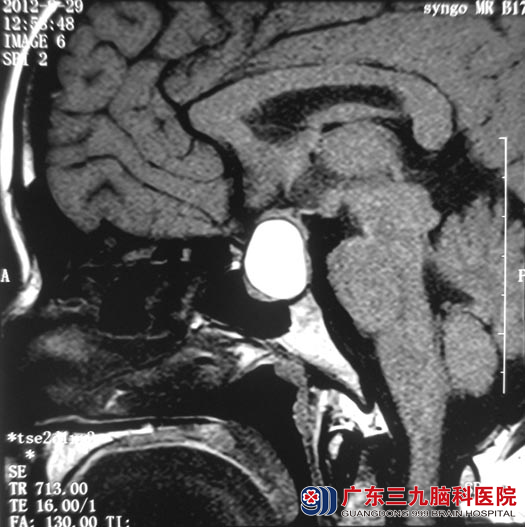

半年前李女士出现月经停止,并伴有睡眠障碍。在当地医院就诊,检查泌乳素:111.83ng/ml(女性未怀孕正常值:2.8-29.2 ng/mL),头颅MR检查:提示鞍区占位,考虑垂体腺瘤伴卒中。

▲手术前